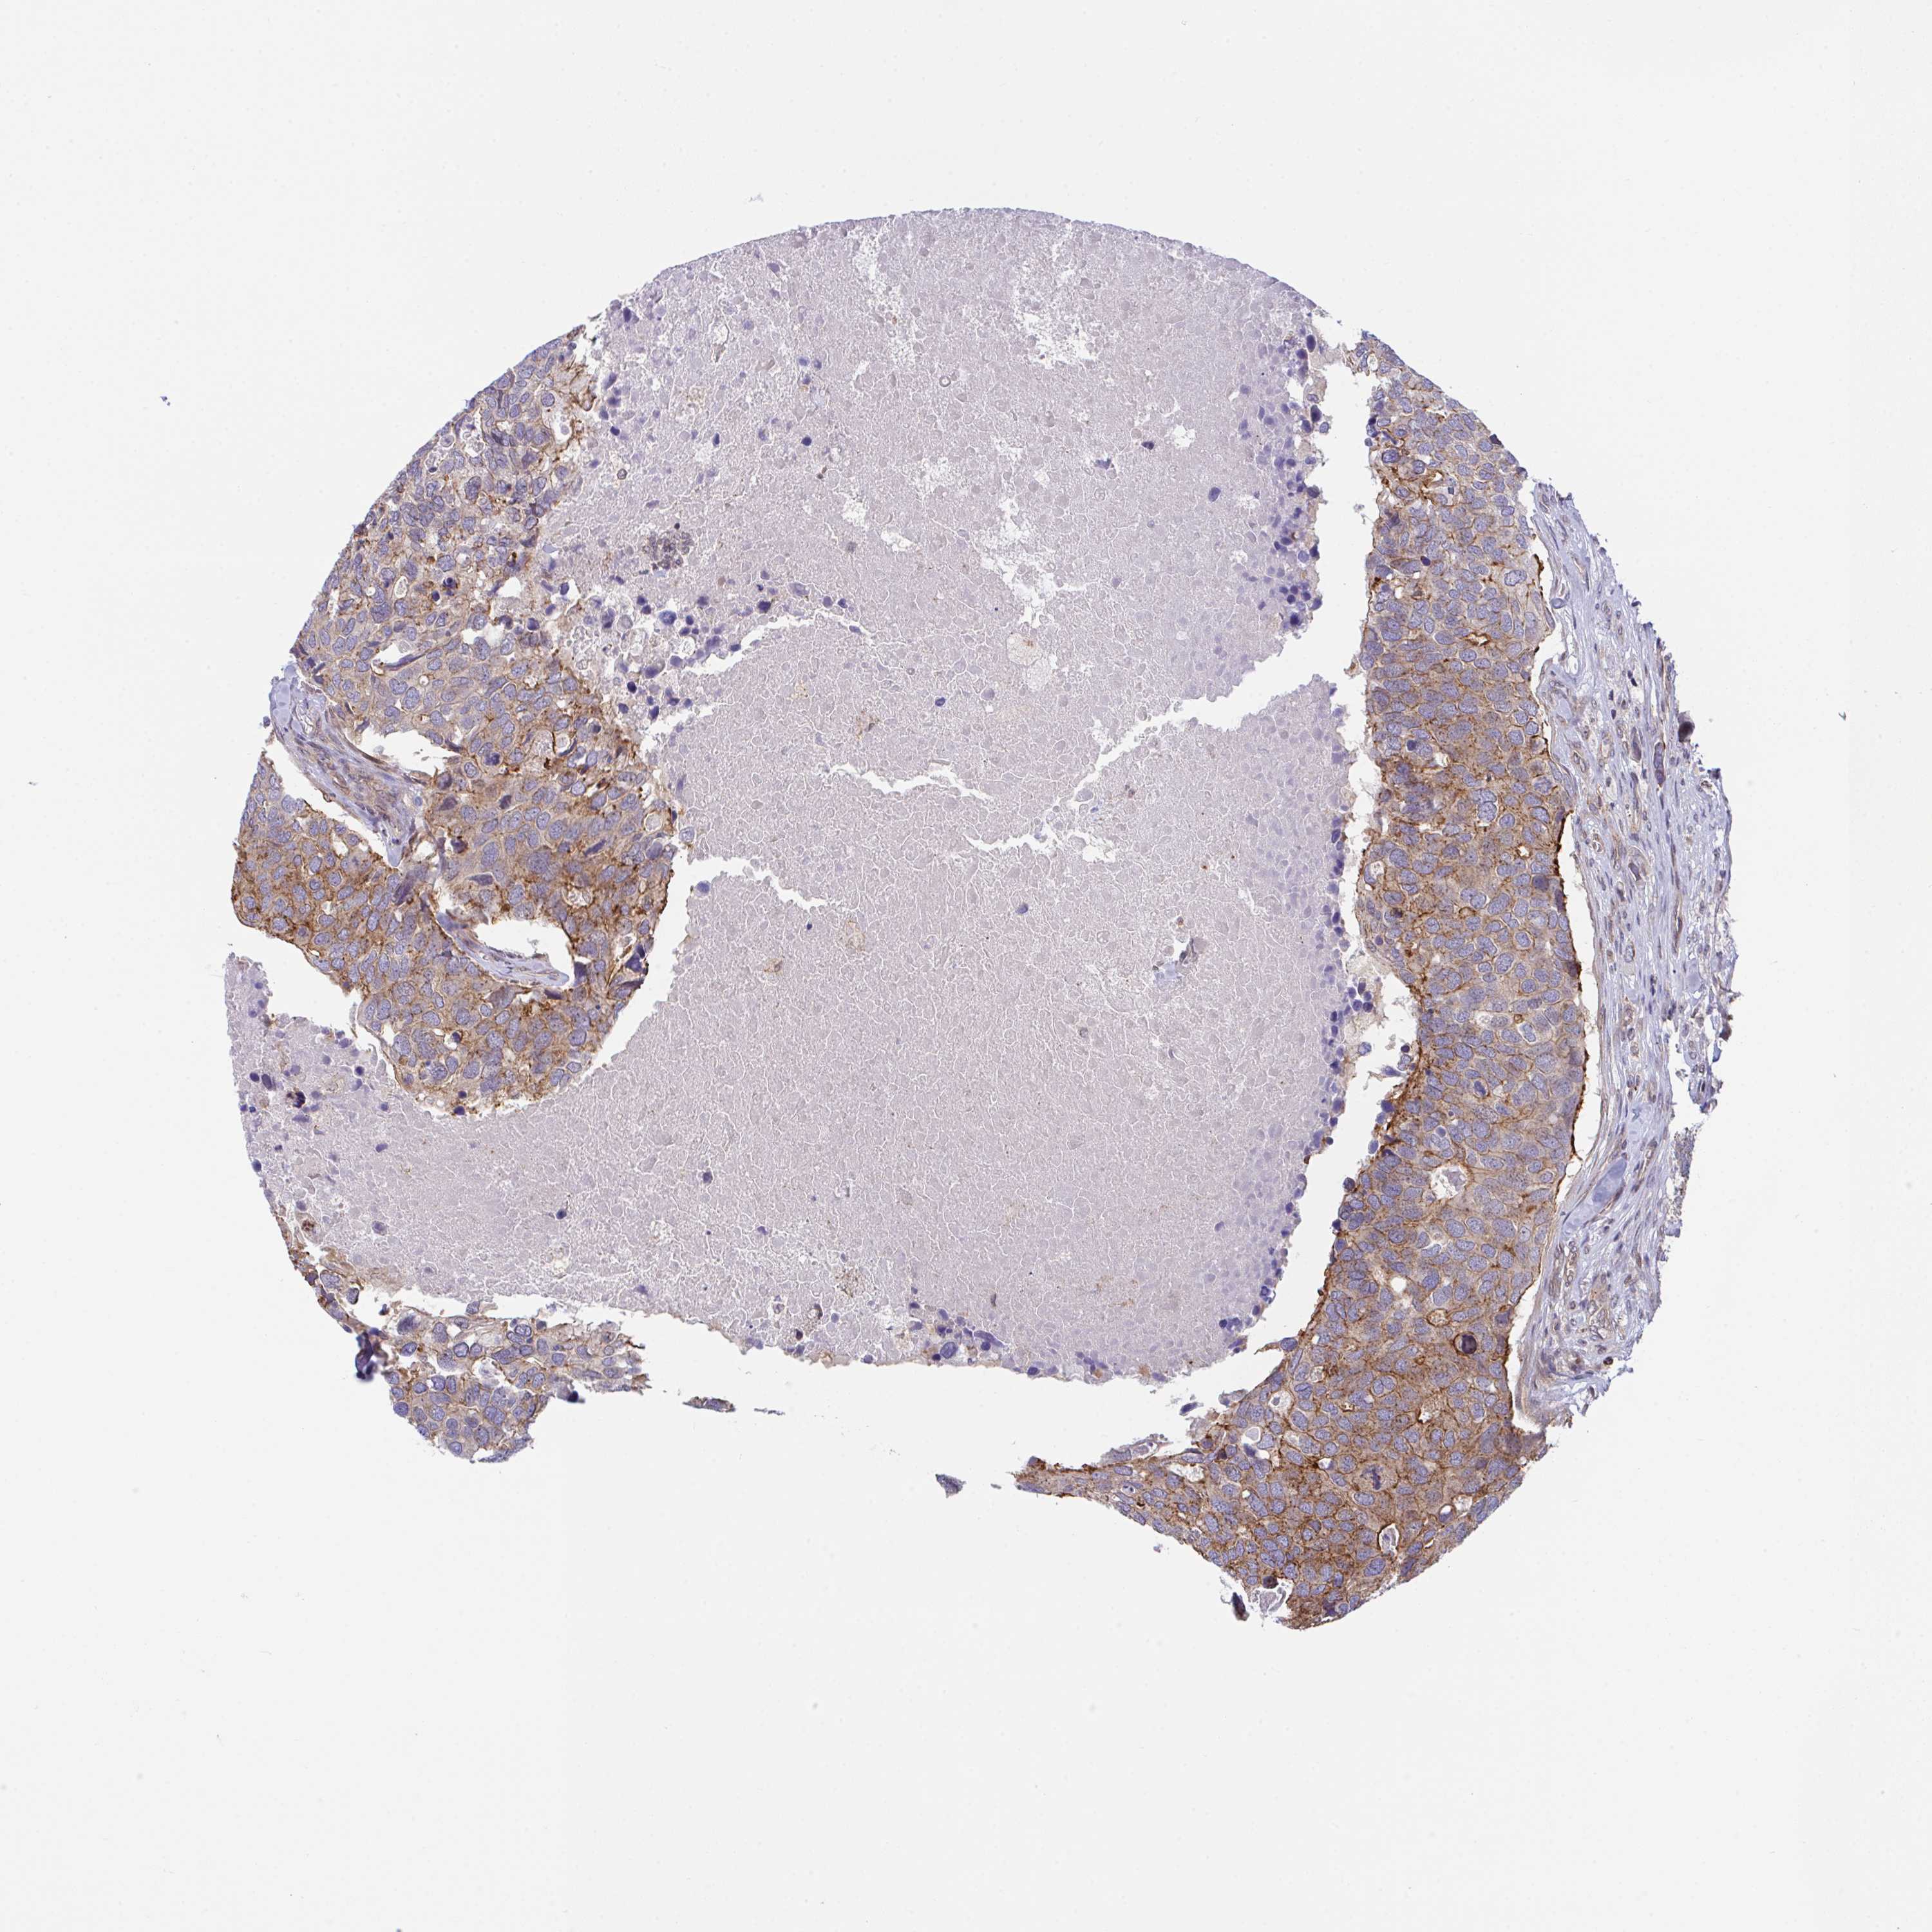

CANCER BREAST CANCER Show tissue menu

BRCA TCGA BRCA VALIDATION PROTEIN EXPRESSION